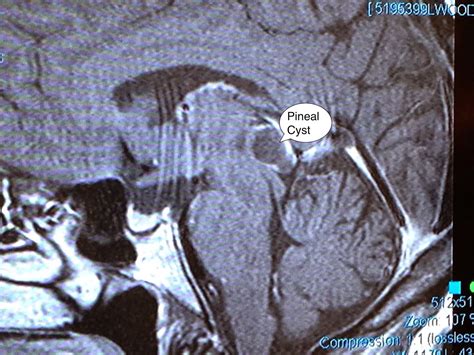

Diagnosing and Monitoring

In most instances, a Pineal Gland Cyst is discovered incidentally. Once identified, neuroradiologists evaluate the cyst using magnetic resonance imaging (MRI). The imaging helps determine the size, appearance, and whether the cyst is putting pressure on critical brain structures.

• pineal gland cyst mri

• pineal gland cyst radiology